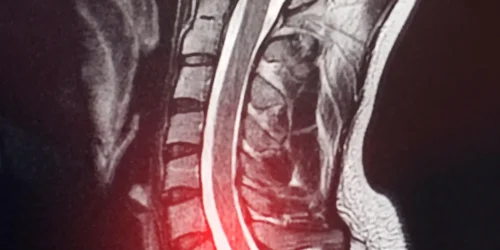

A C6-C7 disc herniation is one of the most common spinal conditions affecting the cervical spine, causing significant pain and…